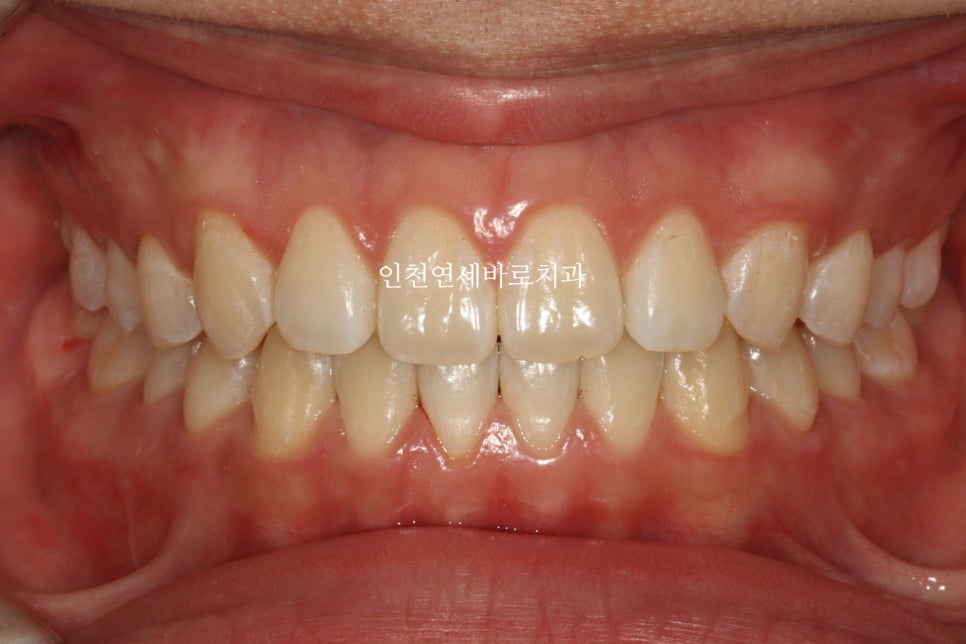

재제작을 통해 제 마음에 안들던 교합까지 형성해드리고, 치아배열도 마무리.

공간도 모두 없어지고 배열도 좋아졌습니다

간단한 교정치료이긴 하지만 제 욕심도 채우고 만족할만한 결과를 얻게 된 환자분의 후기입니다.

벌어진 앞니는 인비절라인의 가장 기초적인 치료 중 하나로, 치료 결과가 매우 좋은 편입니다. 이 케이스에서도 공간이 모두 닫히고 치아 배열이 개선되었습니다.